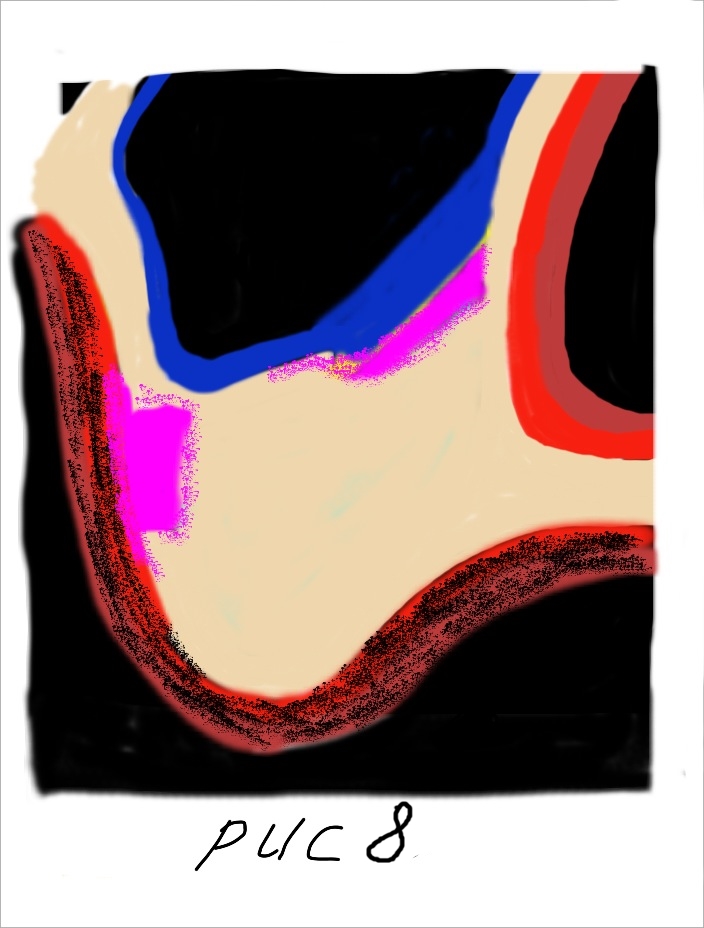

![IMG_2280[1]](http://www.bioimplantat.ru/wp-content/uploads/IMG_22801.jpg) Чем больше соприкосновение биопластического материала с костью и богаче кровоснабжение - тем больше кости Вы получите. Резорбируемые коллагеновые мембраны, такие как Биоматрикс мембрана, в процессе их физиологической реконструкции трансформируются в грубоволокнистую фиброзную ткань, которая формирует дополнительный и надежный барьер между аугментатом и полостью носа.

Чем больше соприкосновение биопластического материала с костью и богаче кровоснабжение - тем больше кости Вы получите. Резорбируемые коллагеновые мембраны, такие как Биоматрикс мембрана, в процессе их физиологической реконструкции трансформируются в грубоволокнистую фиброзную ткань, которая формирует дополнительный и надежный барьер между аугментатом и полостью носа.